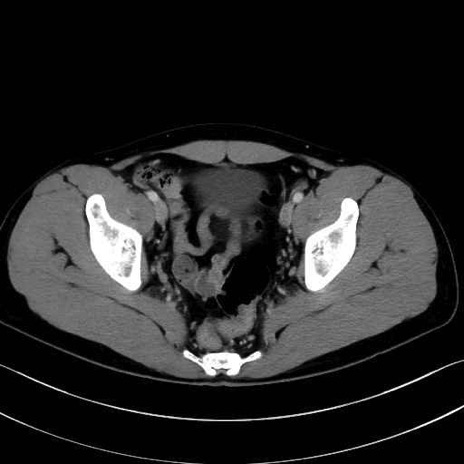

2. 腸腰筋群と骨盤底筋

大腰筋 (Psoas major)

腸骨筋 (Iliacus)

肛門挙筋 (Levator ani)

3. 殿部の筋肉(表層・中層・深層)